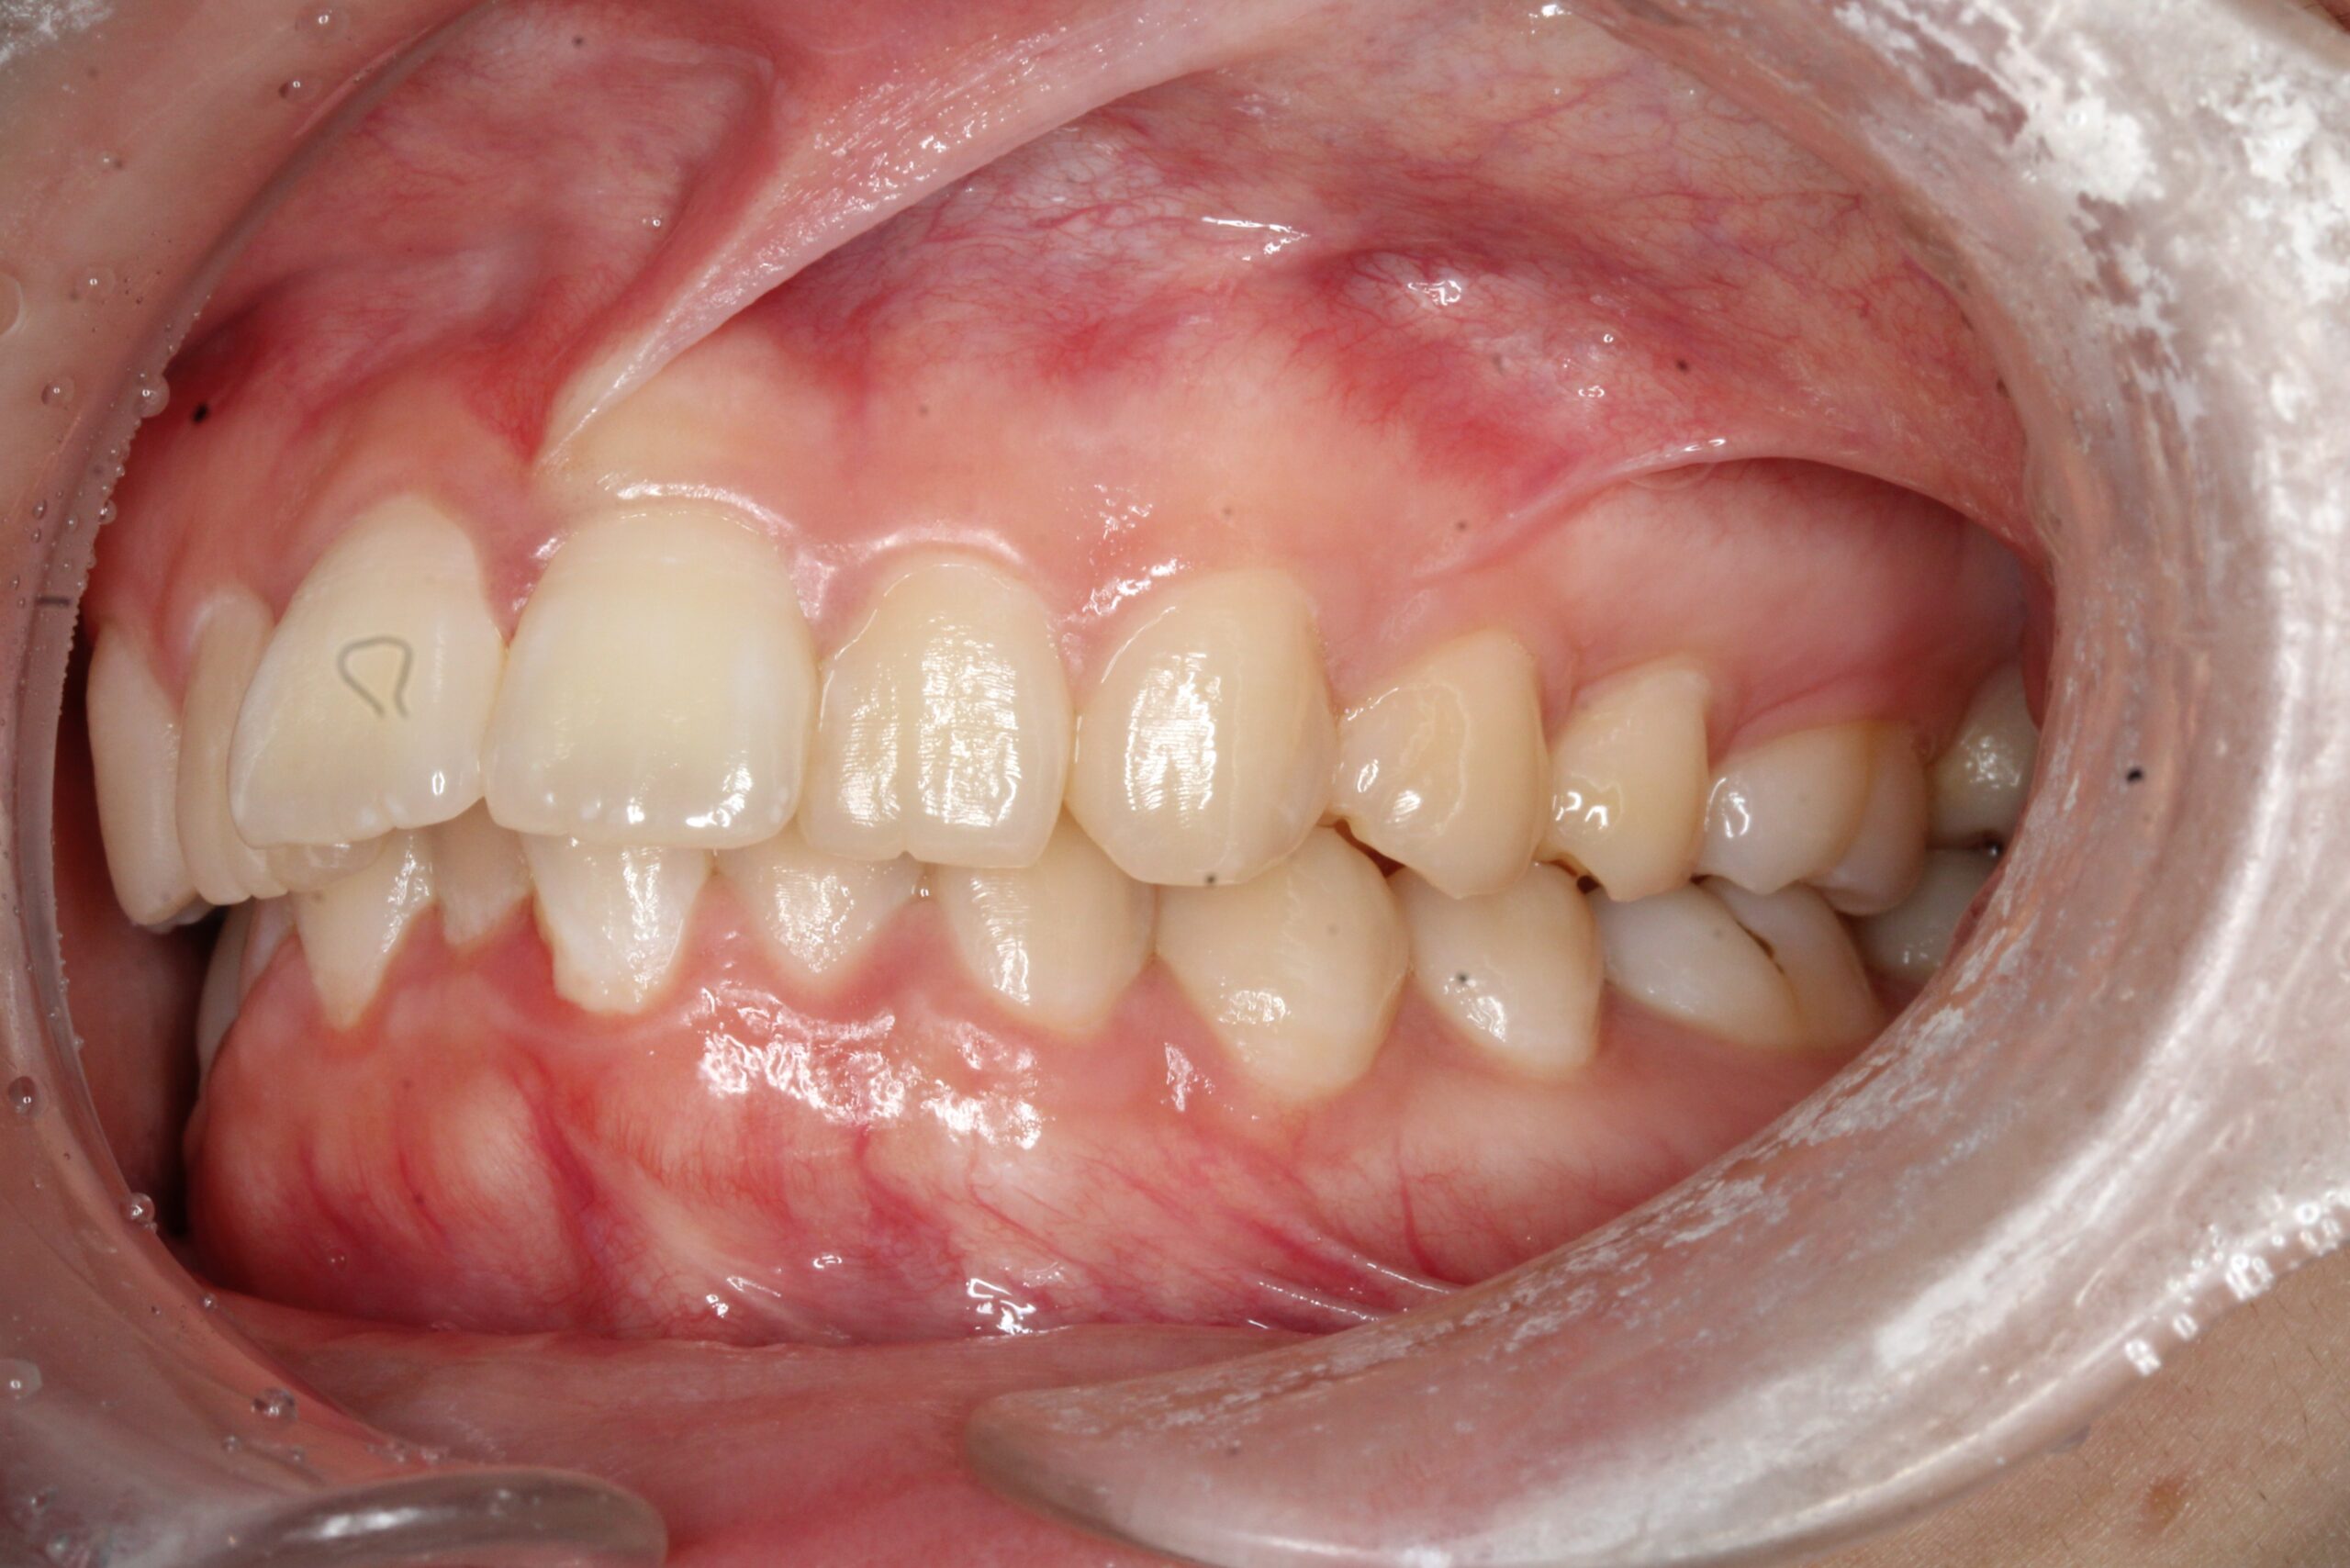

矯正術前:右側

矯正術後:右側